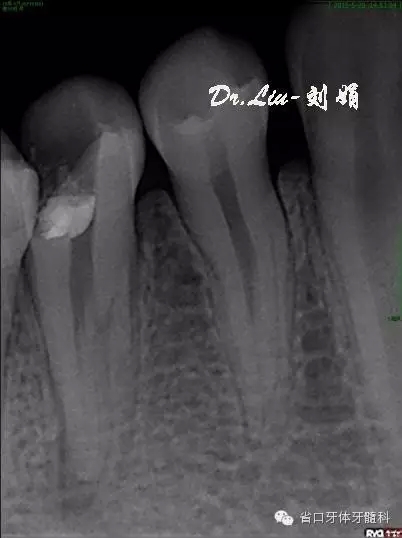

牙片顯示:45充填物至髓腔,根管內(nèi)無充填物影像,根管影像不清疑似多根管,根尖區(qū)見X線透射區(qū)。

圖1:術(shù)前X線片,根管影像不清,根尖區(qū)見X線透射區(qū)